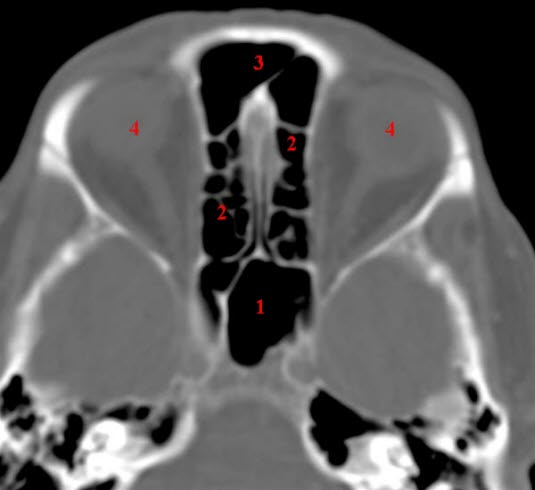

CT-snitt i axialplan gjennom sphenoidalsinus og ethmoidalceller

Basale deler av frontalsinus sees også

- Sphenoidalsinus

- Ethmoidalceller

- Frontalsinus

- Øyne